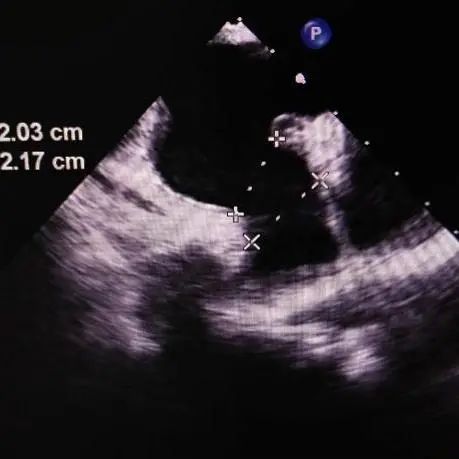

患者全麻后进行左心耳封堵术,在左心耳DSA造影及超声检查下,观察左心耳为菜花型,开口约23mm,锚定区约22mm,选择25mm(固定盘25mm/封堵盘32mm) Amulet左心耳封堵器。

食道超声评估左心耳封堵完全,牵拉稳定,无残余分流,完美释放。手术非常成功。